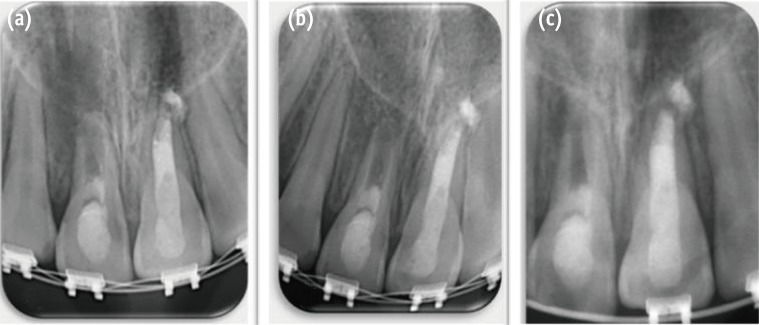

Two weeks later, the tooth was still asymptomatic, and the sinus tract had healed. The tooth was anesthetized with 3% mepivacaine hydrochlor ide without a vasoconstrictor (Polocaine dental, Dentsply Pharmaceutical, York, PA, USA). A rubber dam was placed, and the canal was irrigated with 20 mL of 5.25% sodium hypochlorite to remove the DAP and then rinsed with sterile saline solution and 10 mL of 0.12% chlorhexidine gluconate (Vista Dental, Racine, WI, USA) for 5 minutes. The canal was dried with paper points, and bleeding was induced by gentle irritation of the canal apical tissue with a size 70 K-file (Dentsply Maillefer) (Figure 3a). A layer of 'CollaPlug' resorbable matrix (Zimmer Dental, Carlsbad, CA, USA) was coronally placed over the blood clot to act as a barrier (Figure 3b). A 3 mm thick layer of white MTA (MTA-Angelus, Angelus, Londrina, PR, Brazil) was gently condensed over the CollaPlug matrix to seal the canal system (Figure 3c). A moistened cotton pellet was placed over the MTA, and the access cavity was temporized. The patient returned after 1 week for placement of the final restoration of bonded composite resin (Filtek Z250 XT, 3M ESPE) after removal of the wet cotton pellet and checking the setting of the MTA with an explorer (Figure 3d). The root canal of tooth #21 was cleaned and the apical third was plugged with MTA and the remaining canal was filled with gutta-percha and AH26 sealer (Dentsply De Trey GmbH, Konstanz, Germany). The coronal access was sealed with bonded composite resin.

Figure 3

Second appointment. (a) Bleeding created by overinstrumentation; (b) Bleeding stopped 3 mm from CEJ; (c) Collagen membrane placed on top of the blood clot and placement of white MTA; (d) Access cavity restored with composite resin restoration. CEJ, cementoenamel junction; MTA, mineral trioxide aggregate.

Figure 3 Second appointment. (a) Bleeding created by overinstrumentation; (b) Bleeding stopped 3 mm from CEJ; (c) Collagen membrane placed on top of the blood clot and placement of white MTA; (d) Access cavity restored with composite resin restoration. CEJ, cementoenamel junction; MTA, mineral trioxide aggregate.